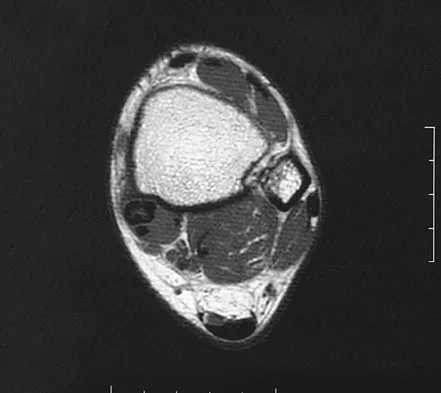

A 39-year-old woman fell onto her flexed elbow and sustained a comminuted displaced radial head and neck fracture. Radiographs confirm concentric reduction of the ulnohumeral joint. Examination reveals pain with compression of the radius and ulna at the wrist. What is the best treatment for the radial head fracture?

Explanation

Patients with comminuted radial neck and head fractures and associated wrist pain have a significant injury to the elbow and forearm. Nonsurgical management is an option, but initial casting will result in stiffness and early range of motion is likely to be unsuccessful secondary to pain. Surgical treatment with open reduction and internal fixation, although possible, is technically demanding and results are unpredictable with comminuted fractures. Excision alone in the face of wrist pain may lead to radial shortening. The treatment of choice is excision and metallic radial head arthroplasty. Silastic implants have been associated with synovitis and wear debris. Furry KL, Clinkscales CM: Comminuted fractures of the radial head: Arthroplasty versus internal fixation. Clin Orthop 1998;353:40-52.